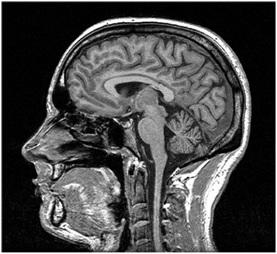

MRI stands for Magnetic Resonance Imaging. This technology relies on magnetism. It’s a more recent advancement compared to CT scans. MRI uses magnetism to create a 3D image of the body’s interior.

Similar to CT scanners, MRI machines have a moving platform. Patients lie down on this platform and are moved into a narrow cylinder. Magnets within the cylinder generate a strong magnetic field around the patient’s body. The cylinder is somewhat narrower compared to CT scanners. It’s crucial to remove all metallic objects from the body before an MRI scan. MRI scans can take around 30 minutes to complete.